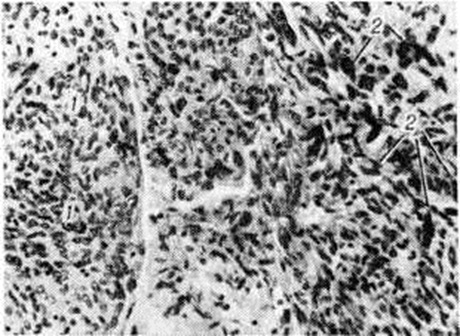

Рис. 2.

Микропрепарат фибробластической менингиомы: пучки фибробластоподобных вытянутых клеток указаны стрелками; окраска гематоксилин-эозином; × 240.